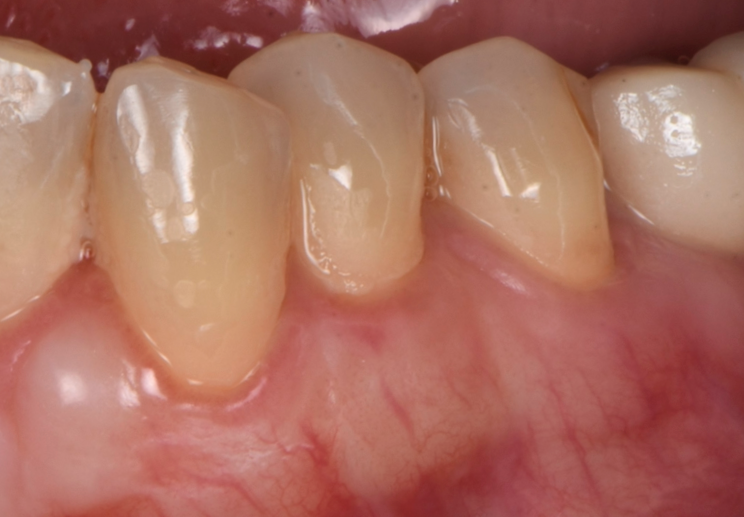

Una vez que hemos perdido encía y se ha quedado la raíz dental expuesta, podemos realizar cirugía mucogingival para volver a recuperar la estética y salud de nuestro periodonto.

Casos clínicos realizados por el Dr. Alfonso García

Antes

Caso 2